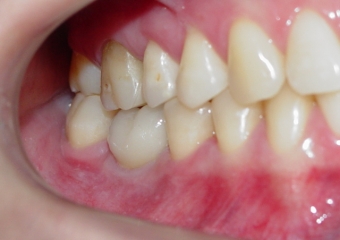

Imagens da prótese unitária sobre implante, do caso finalizado em janeiro de 2011